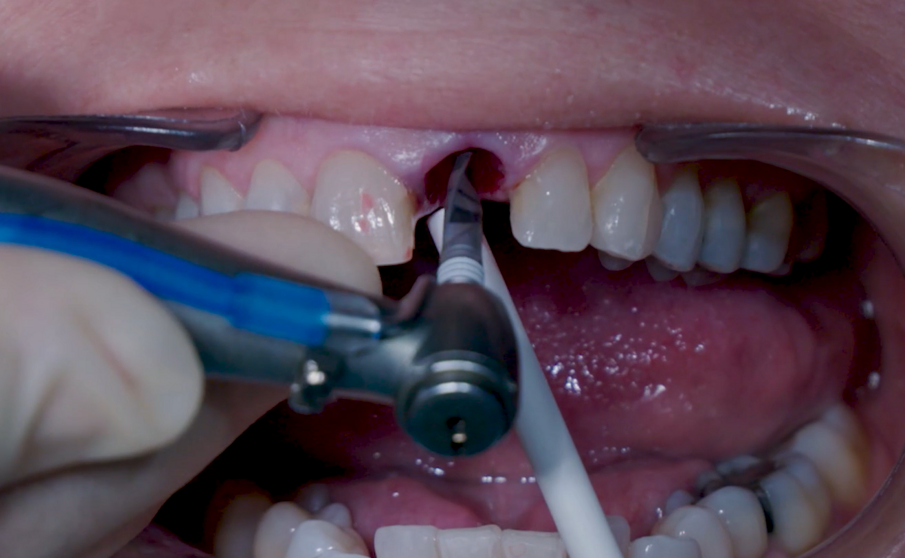

Sono state eseguite incisioni intrasulculari per liberare le fibre gengivali marginali in modo da consentire un’estrazione minimamente invasiva. L’alveolo è stato accuratamente pulito per rimuovere eventuali residui di legamenti e detriti. Particolare attenzione è stata data alla valutazione dell’integrità della parete alveolare. È stata rispettata una distanza di 3 mm tra il margine gengivale e il margine della parete vestibolare. La preparazione del sito implantare è stata considerata flusso di lavoro osseo di media densità, partendo dalla fresa appuntita in direzione della parete palatale per creare un punto d’ingresso per le frese successive, realizzando un’osteotomia per consentire una più ampia zona di ingresso dell’impianto (Fig. 5).

La fresa preliminare da Ø 2,2 mm è stata utilizzata sulla rispettiva lunghezza prevista dall’impianto, seguita da un perno di allineamento per controllare l’orientamento in 3D (Figg. 6, 7). Le frese da Ø 2,8 mm e Ø 3,2 mm sono state utilizzate per completare l’osteotomia (Fig. 8). Il sito è stato quindi opportunamente sondato per valutare la possibile perforazione della parete. Un impianto 4×14 mm è stato posizionato, a partire dalla maniglia chirurgica che coinvolge la parte apicale dell’impianto, seguendo lo stesso orientamento dell’ago perforatore e correggendo la direzione dell’impianto mentre si spostava all’interno dell’osteotomia (Figg. 9, 10). La stabilità primaria (45 Ncm) è stata raggiunta nella posizione finale.